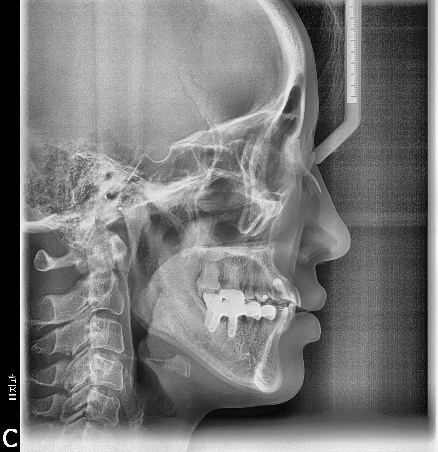

마무리된 교합은 초진시에 동일하게 양측 Class 1 교합으로 마무리하였으며 측모두 부방사선 사진에서 보듯 교정중 발생했던 전치의 flare가 개선되었습니다.

구치부 상실시 임플란트 조기식립은 고정원 확립에 있어 상당한 장점을 가지고 있으므로 대합치와 인접치의 최종위치를 예상해 정확한 위치에 식립될 경우 교정치료에 유용하게 이용할 수 있다고 생각됩니다.

최종적으로 대합치의 상태를 보고-특히 교정을 먼저한 경우는 원래의 해부학적위 치와 달라지는 경우가 있을 수 있기 때문에 이러한 여러요소들을 고려해서 임플란트식립과 보철을 마무리하는 것이 좋습니다. 위의 증례에서는 이종골과 흡수성막을 통한 수평골확장술을 시행하며 4.5와 5.0직경의 8mm임플란트로 마무리하였습니다.